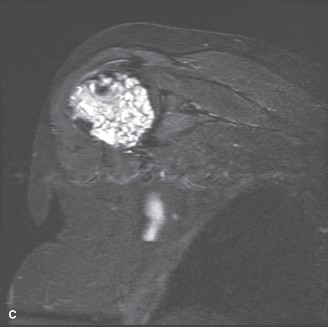

Axial T2-weighted and STIR (Short Tau Inversion Recovery) sequences revealed the classic hyperintense, lobulated appearance of hyaline cartilage. The high water content of the cartilaginous matrix results in a bright signal on fluid-sensitive sequences. Low-signal septations were visualized between the cartilaginous lobules. Importantly, the MRI confirmed the absence of a soft tissue mass and verified that the cortical boundary, while severely thinned, remained intact.

Post-contrast T1-weighted fat-saturated images demonstrated peripheral and septal enhancement. This "rings and arcs" enhancement pattern is typical for cartilaginous lesions. The lack of diffuse, solid enhancement helped rule out a higher-grade chondrosarcoma or a dedifferentiated component. However, the presence of peritumoral bone marrow edema was noted, which is a secondary sign of biologic activity and microtrabecular stress, further supporting the diagnosis of an ACT over a quiescent enchondroma.